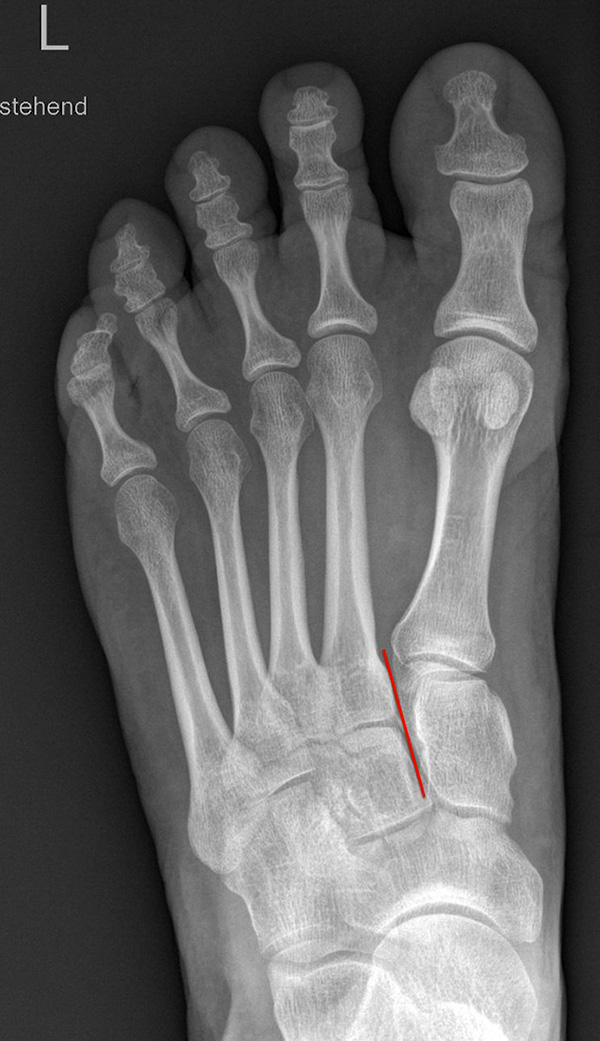

Auf den dp-Aufnahmen sollte der mediale Rand der Metatarsale-2-Basis mit dem medialen Rand des Os cuneiforme intermedium eine homogene Linie ohne Stufenbildung bilden (Abb. 7+8). Außerdem ist auf den Abstand zwischen der Metatarsale-1- und -2-Basis zu achten. Dieser sollte nicht größer als 2 mm bzw. im Vergleich zur Gegenseite nicht mehr als 1 mm erweitert sein. In bis zu 90% der Fälle zeigt sich ein sogenanntes „Fleck sign“ (Abb. 9), ein knöchernes Fragment zwischen der Metararsale-1- und -2-Basis im Sinne eines knöchernen Ausrisses des Lisfranc-Ligaments an der Metatarsale-2-Basis 211936410. Oft liegen zusätzliche Frakturen der Metatarsalebasen oder der Tarsale vor, die ebenfalls identifiziert werden sollten. Bei jeder Mittelfußbasisfraktur sollte umgekehrt an eine Lisfranc-Verletzung gedacht werden.

Zum Lesen der Bildbeschreibung und zur Vollansicht bitte die Bilder anklicken.

In der Schrägaufnahme sollte der mediale Rand des Cuboids mit dem medialen Rand der Metatarsale-4-Basis eine homogene Linie bilden.